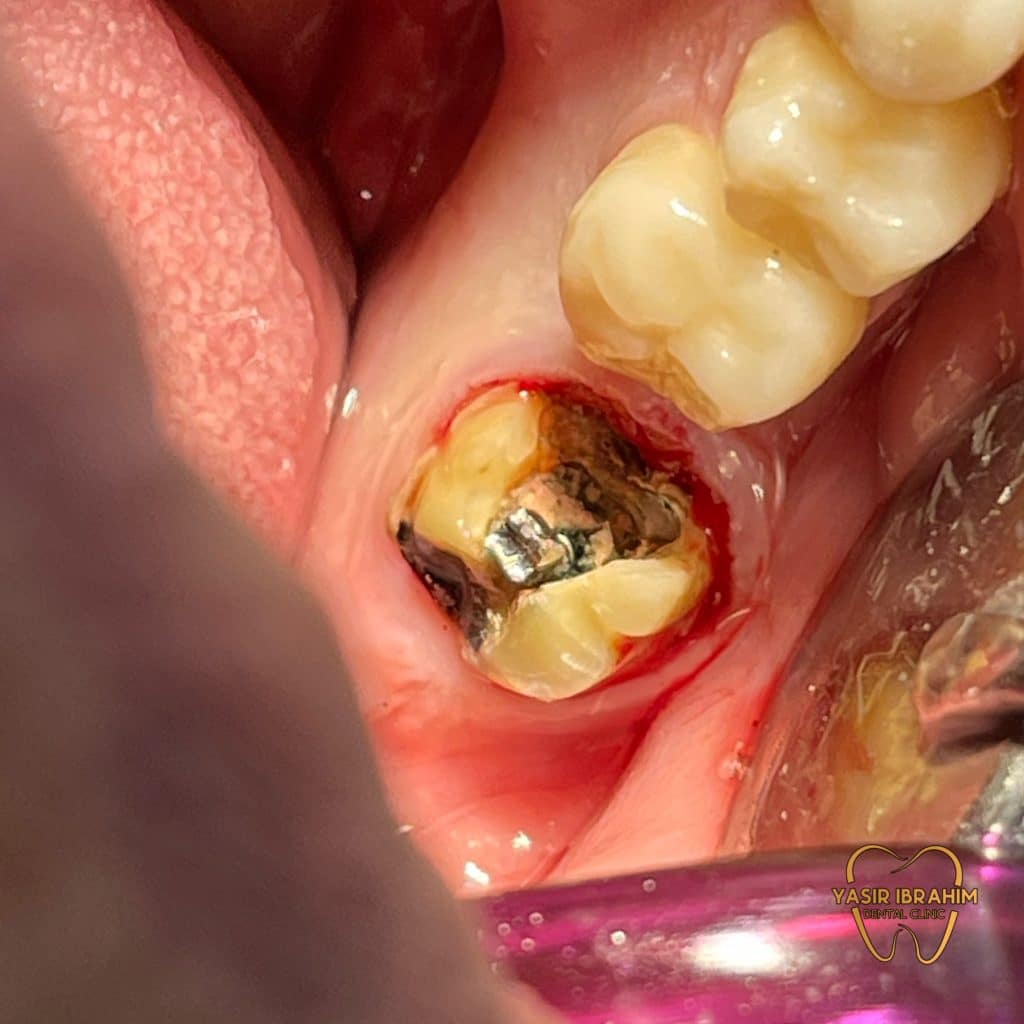

1_remove the crown .

Pus drainage through the root canal system After emergency A.O

Complete cleaning.

c-shape canal.